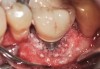

Clinical examination showed 2 mm of buccal recession with a shallow vestibule and absence of keratinized attached gingiva against the crown with 8 mm of circumferential pocketing accompanied by bleeding upon probing (Figure 15 and Figure 16). A periapical radiograph showed a symmetrical vertical osseous defect causing the loss of 50% of the bone around the implant (Figure 17). Because the patient had made a significant investment of time and finances to replace her lost tooth with the implant, she desired that the implant and restoration be retained, if feasible.

A surgical flap procedure was performed with the intent of thoroughly debriding the granulomatous tissue from the osseous defect (Figure 18 and Figure 19), mechanically and chemically detoxifying the surface of the implant (Figure 20 through Figure 22), and grafting the infrabony component of lesion with bone xenograft (Bio-Oss®, Geistlich Pharma, www.geistlich-na.com) in an attempt to reduce the vertical defect (Figure 23). To concurrently resolve the mucogingival problem, the plan called for placing a dermal allograft (Dermis Allograft, DENTSPLY International, www.dentsply.com) on the buccal (Figure 24) and then replacing the flap (Figure 25).

Fig 15. The implant-supported restoration of tooth No. 19 presented with a lack of attached keratinized gingiva, shallow buccal vestibule, and 2 mm of buccal recession.

Fig 16. The restoration exhibited an 8-mm pocket upon probing, with bleeding on the buccal aspect.

Fig 18. A full-thickness flap from teeth Nos. 18 to 20 revealed granulomatous tissue in the circumferential defect around implant No. 19.

Fig 19. The circumferential defect was debrided. Note excess cement extending apically from the margin of the crown into the defect; residual cement has been shown to be complicit in the development of peri-implant disease.